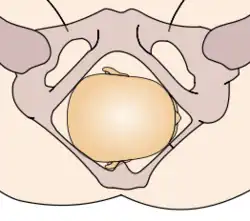

Durante la mecánica del parto, los diámetros menores del feto pasan por los diámetros mayores de la pelvis materna. Con el fin de no quedar encajado en algún punto durante su trayectoria fuera del útero, el neonato pasa por una serie de movimientos naturales que constituyen el mecanismo del parto.

- Descenso: ocurre por acción de la gravedad una vez dilatado el cuello uterino, así como de las poderosas contracciones uterinas y de los músculos abdominales maternos. El descenso tiende a ser lentamente progresivo basado en la estructura pélvica materna.

- Flexión: la cabeza del feto se flexiona, de modo que el mentón fetal hace contacto con su pecho, al encontrarse el primer punto de resistencia del piso pélvico.

- Encajamiento: el diámetro de la cabeza del feto que va desde un hueso parietal al opuesto, llamado diámetro biparietal, alcanza el estrecho superior de la pelvis a nivel de las espinas isquiáticas. Por lo general ocurre en la fase tardía del embarazo, justo al iniciarse el trabajo de parto.

- Rotación interna: ocurre en el estrecho medio de la pelvis, cuando el feto, al continuar su descenso, hace una rotación de 90° en el sentido contrario a las agujas del reloj, de modo de adaptarse a la configuración romboidal de los músculos del piso pélvico, entre el músculo elevador del ano y los ileocoxígeos. Así, la cara del bebé está dirigida mirando hacia el recto materno.

- Extensión: la cabeza del feto atraviesa el canal del parto, se extiende de tal manera que la frente se desplaza primero por el orificio vulvar. La cabeza está por debajo de la sínfisis púbica y ha distendido al máximo el perineo.

- Rotación externa: una vez que ha salido la cabeza, se gira 45° para restaurar su posición original antes de la rotación interna y quedar en posición normal en relación con los hombros. Se denomina por ella la restitución, haciendo el paso de los hombros más factible.

- Expulsión: el hombro púbico tiende a salir primero, seguido por el hombro perineal. El resto del cuerpo sale por sí solo con una leve impulsión materna.

Estos movimientos son todos debido a la relación que existe entre la cabeza ósea y hombros del feto y el anillo óseo de la pelvis materna.

La relación de la fontanela posterior con la pelvis materna determina el diagnóstico de posición. Se distinguen ocho posiciones en la presentación de vértice: I. Occípito ilíaca izquierda anterior (OIIA) en que la fontanela posterior se ubica hacia delante en relación con la pelvis materna y además a la izquierda de la madre. La sutura sagital está orientada oblicuamente. II. Sucesivamente dependiendo de la ubicación de la fontanela posterior (porque la pelvis es siempre la misma) las posiciones serán: